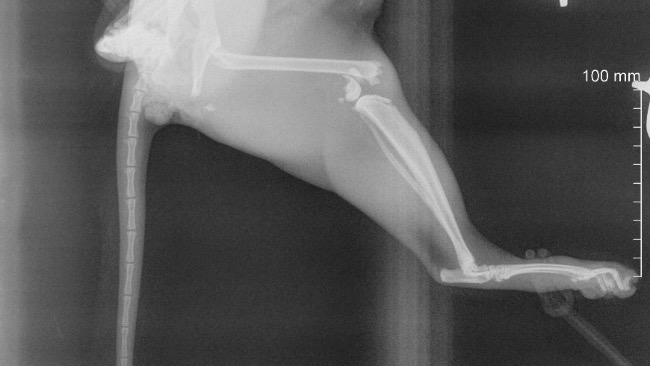

KOTKA W DNIU JUTRZEJSZYM (27.12- najszybszy termin) ZOSTANIE ZOPEROWANA

Wszystkim, którzy w jakimkolwiek większym lub mniejszym stopniu dołożyli się do zbiórki jestem naprawdę wdzięczna. Kotka ma się dobrze, już jutro zostanie poddana amputacji (była zabezpieczona oczywiście lekami do tego czasu). Zbiórkę zamykam, ponieważ resztę środków udało mi się pozyskać prywatnie. Dziękuję raz jeszcze każdemu z osobna.

Witam, niestety z bólem serca muszę szukać pomocy w świecie. Święta w tym roku już nie będą miały żadnej magii, ponieważ nasza kochana kotka Cleo uległa wypadkowi. Nie chcę jej usypiać, ponieważ jest półtorarocznym maleństwem i ma przed sobą całe życie. Jednakże koszt amputacji i dalszego leczenia na ten moment mnie przerasta, a biedna kotka czeka na decyzję w sprawie jej życia. Licze tylko i wyłącznie na świąteczny cud🥹